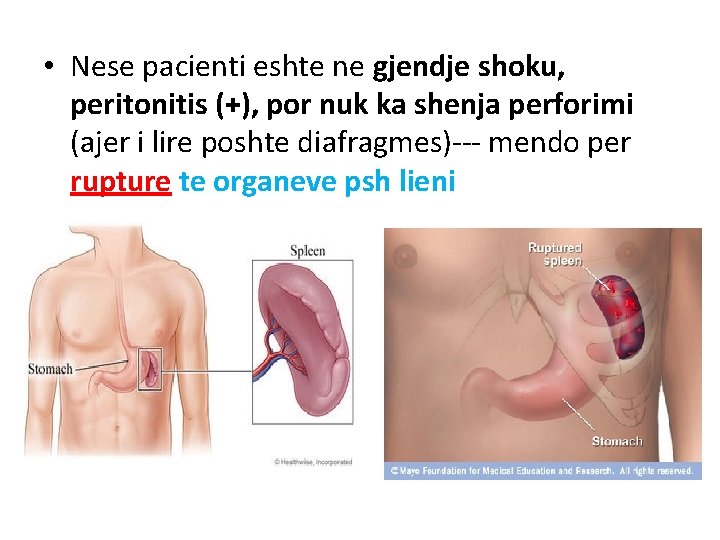

• Nese pacienti eshte ne gjendje shoku, peritonitis (+), por nuk ka shenja perforimi (ajer i lire poshte diafragmes)--- mendo per rupture te organeve psh lieni